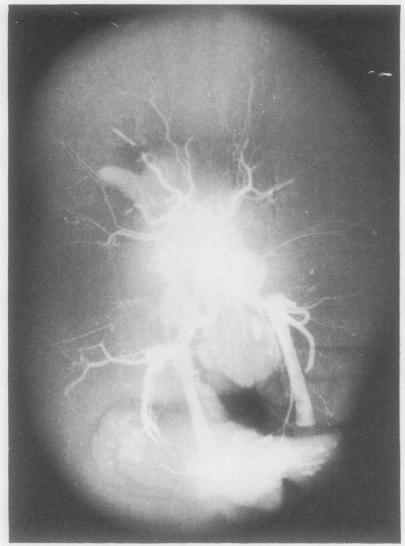

Examination of products of conception terminated after prenatal investigation.

A large number of district general hospitals have access to diagnostic ultrasonography and other methods of prenatal diagnosis, resulting in an increased supply of freshly terminated malformed fetuses to general histopathology departments, and there is now more open discussion of malformation and greater concern over fetal wastage. General pathologists are therefore under greater pressure to produce complete and detailed descriptions of a wide range of often complex anomalies. The dismissal of specimens as "multiple congenital anomalies" is becoming increasingly unacceptable to couples who wish to embark on further pregnancies and to their medical attendants. As in other fields an understanding of the methods and terminology in clinical use and a consistent diagnostic approach should help pathologists to extract sufficient information for accurate counselling.